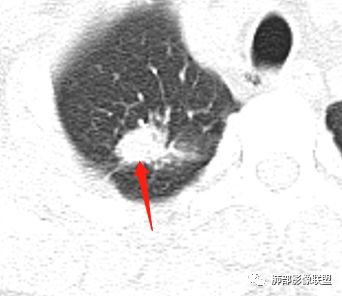

右肺上叶病灶两部分

纵隔窗提示内侧部分密度不够实

左肺尖及右肺病灶附近见小斑点,边界尚清

这些是否是边界清楚GGO?

南边:2、不踏实的地方:GGO是不是容积效应所致?如果薄层,边界清楚GGO,就考虑继发瘢痕癌